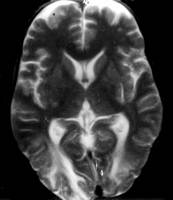

Totusi TUNCAY si colab. au sesizat implicarea precoce a substantei cenusii, studiul lor evidentiind leziuni predominante la nivelul substantei cenusii si al substantei albe subcorticale (62). Leziuni descrise de ei sunt asimetrice si afecteaza preponderent partea posterioara a emisferelor cerebrale (fig. 3). Tardiv, ei au observat modificari de hipersemnal in structura profunda a substantei albe, si anumite grade de atrofie cerebrala. Leziunile parenchimatoase au fost corelate cu durata bolii.

Figura 3: imagine prin rezonanta magnetica avand

predominanta T2, prezentand zone hiperintense in ambele

regiuni occipitale.